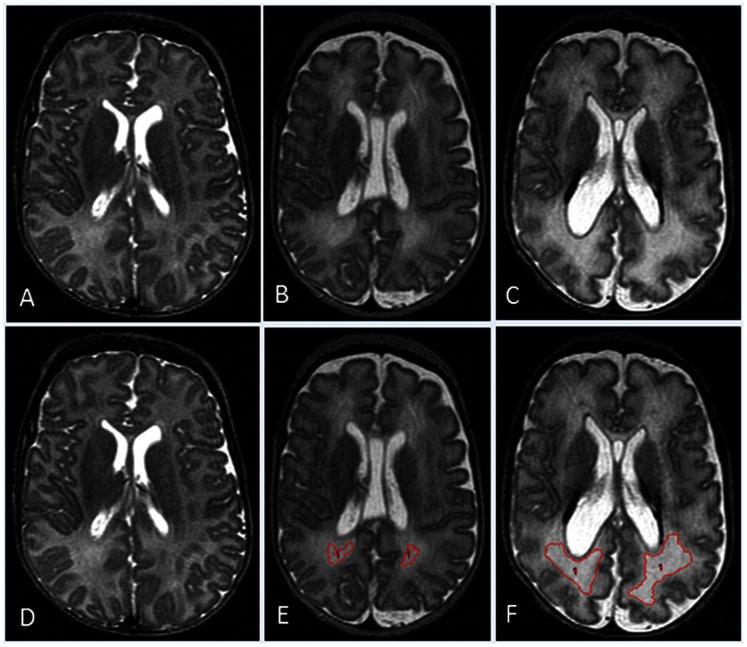

Our objective was to investigate diverse clinical antecedents of total and regional brain volume abnormalities and white matter hyperintensity volume on term MRI in extremely low birth weight (birth weight ≤1000 g) survivors. A consecutive cohort of extremely low birth weight infants who survived to 38 weeks postmenstrual age (n = 122) and a control group of 16 healthy term newborns underwent brain MRI at term-equivalent age. Brain volumes were measured using semi-automated and manual segmentation methods. Using multivariable linear regression, clinical antecedents were correlated with volumes of total brain tissue, white matter hyperintensities, and regional tissues/structures, adjusted for age at MRI, total cranial volume, and total tissue volume. Regional brain volumes were markedly reduced in extremely low birth weight infants as compared to term newborns (relative difference range: -11.0%, -35.9%). Significant adverse clinical associations for total brain tissue volume included: small for gestational age, seizures, caffeine therapy/apnea of prematurity, duration of parenteral nutrition, pulmonary hemorrhage, and white matter injury (p<0.01 for each; relative difference range: -1.4% to -15.0%). Surgery for retinopathy of prematurity and surgery for necrotizing enterocolitis or spontaneous intestinal perforation were significantly associated with increasing volume of white matter hyperintensities. Regional brain volumes are sensitive to multiple perinatal factors and neonatal morbidities or interventions. Brain growth measurements in extremely low birth weight infants can advance our understanding of perinatal brain injury and development.

我们的目的是研究极低出生体重(出生体重≤1000g)幸存者足月 MRI 上总脑体积和区域性脑体积异常及脑白质高信号体积的不同临床前因。连续纳入了 122 例极低出生体重且能存活至校正胎龄 38 周的婴儿和 16 名健康的足月儿作为对照组,两组均在校正胎龄时行脑部 MRI。使用半自动和手动分割方法测量脑容量。采用多元线性回归,校正 MRI 时的年龄、颅腔总容积和总组织容积后,将临床前因与总脑组织体积、脑白质高信号体积和区域性组织/结构体积相关联。与足月儿相比,极低出生体重儿的区域性脑容量明显减少(相对差异范围:-11.0%至-35.9%)。总脑组织体积的不良临床关联因素包括:小于胎龄儿、癫痫发作、咖啡因治疗/早产儿呼吸暂停、肠外营养时间、肺出血和脑白质损伤(每个因素的 p 值均<0.01;相对差异范围:-1.4%至-15.0%)。早产儿视网膜病变的手术和坏死性小肠结肠炎或自发性肠穿孔的手术与脑白质高信号体积增加显著相关。区域性脑容量对多种围产期因素、新生儿并发症或干预措施敏感。极低出生体重儿的脑生长测量可增进我们对围产期脑损伤和发育的认识。